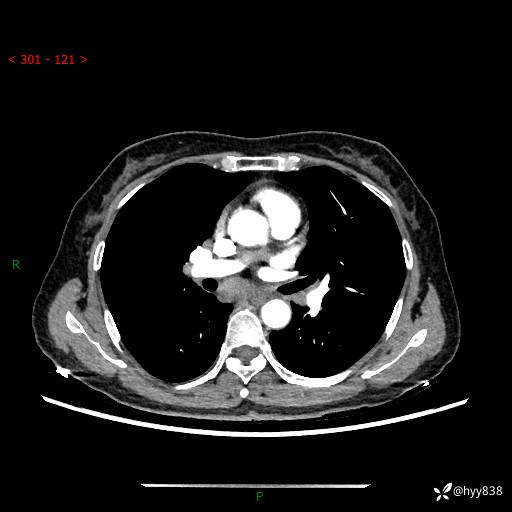

【患者信息】:58岁/女

【主诉】:体检发现肺结节

【检查】:胸部CT平扫+增强

结节病 (44)

小细胞癌 (19)